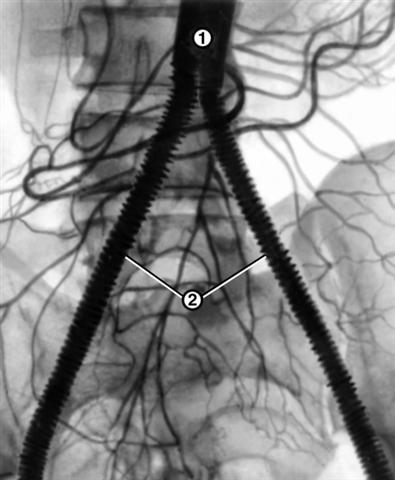

Рис. 3. Аортограмма больного с синдромом Лериша после резекции брюшной части аорты с бифуркационным протезированием: 1 — аорта; 2 — сосудистый протез, идущий от аорты к глубоким артериям бедер.